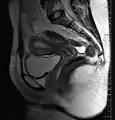

رنين مغناطيسي سهمي يعرض مكان المهبل، وعنق الرحم، والرحم

الأعضاء الجنسية الأنثوية الداخلية هي المهبل، والرحم، وقنوات فالوب، والمبيضين.[3][3]